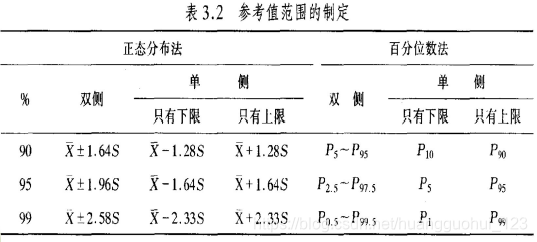

制定参考值范围的步骤:

- 选择足够数量的正常人作为调查对象。

- 样本含量足够大。

- 确定取单侧还是取双侧正常值范围。

有些指标过高过低都是异常的,我们需要制定双侧的正常值范围

有些指标过低才是异常的,比如肺活量,我们只要制定单侧的正常值范围

- 选择适当的百分界限。

在实际操作当中,我们一般将正常人中的5%排除在外,计算95%参考值范围。

- 选择适当的计算方法。

正态近似法:适用于正态分布或近似正态分布的资料。

百分位数法:适用于偏态分布资料。